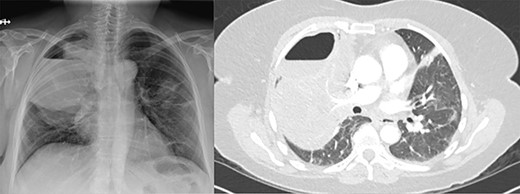

Three weeks following her initial COVID-19 diagnosis, she presented to the hospital with ongoing symptoms and was found to have a right hydropneumothorax and cavitary lesion with parenchymal destruction (Fig. 1). She was treated with broad-spectrum antibiotics and percutaneous chest tube drainage, which showed a continuous one- to two-column air leak. Her pleural fluid grew methicillin-sensitive S. aureus (MSSA). Bronchoscopy revealed mucosal edema and erythema, particularly in the right upper lobe. Despite treatment, she had a persistent air leak, and she was transferred to our facility for further management.

(A) Plain film of chest showing apical hydropneumothorax. (B) Computed tomography axial image demonstrating a complex hydropneumothorax with significant right sided parenchymal infiltrate.